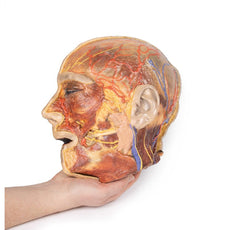

3D Printed Sagittal Section of Head with Infratemporal Fossa Dissection

This 3D model provides a combined midsagittal section through the head and

superior neck coupled with a deep dissection into the infratemporal fossa

region and superficial dissection of the scalp.

On the opposing side of the model, a superficial and deep dissection has

opened a large window into the anatomy of the lateral scalp and infratemporal

fossa. Across the scalp there is a well preserved posterior auricular nerve

and superficial temporal artery highlighted on the superficial surface of the

temporalis muscle. Anteriorly, the temporalis has been dissected to expose

the deep temporal arteries arising from across the maxillary artery.